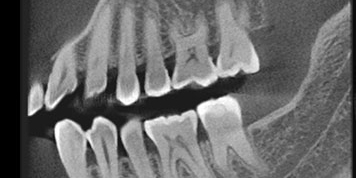

More detail, more confidence

70μm resolution @ 4x3cm

Superior image processing technology